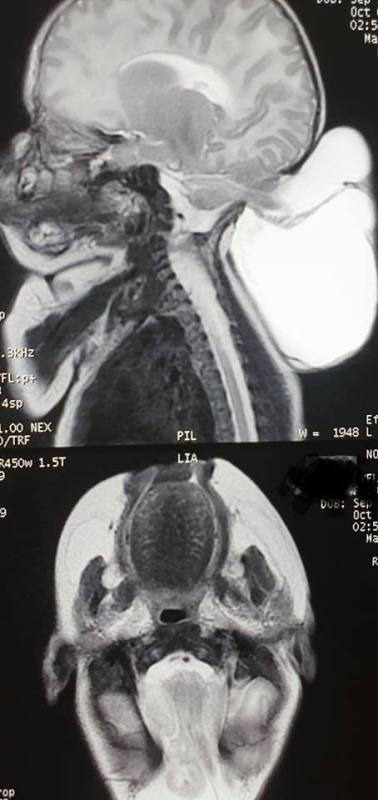

«Дитина мала ваду розвитку нервової системи – енцефалоцелє (черепно-мозгова грижа) та важку вроджену ваду серця – двокамерне серце з атрезією трустулкового клапана і недорозвинутим стовбуром легеневої артерії», – розповів лікар.

«Зважаючи на те, що вада серця у новонародженої дитини є дуже серйозною, мультидисциплінарною командою нашої лікарні було прийнято рішення про оперування черепно-мозкової грижі у дівчинки, адже грижовий мішок був значних розмірів і мав тенденцію до розриву. Ризик до оперативного втручання, а особливо до анестезіологічного був надзвичайно великим. Потрібно розуміти те, що дитина з такою вадою серця могла взагалі не дожити до дня цієї невідкладної операції», – пояснив Тарас Микитин.

Дівчинка була прооперована 9 жовтня нейрохірургами Тарасом Микитиним, Ігорем Гоменюком та анестезіологом Сергієм Шишом.